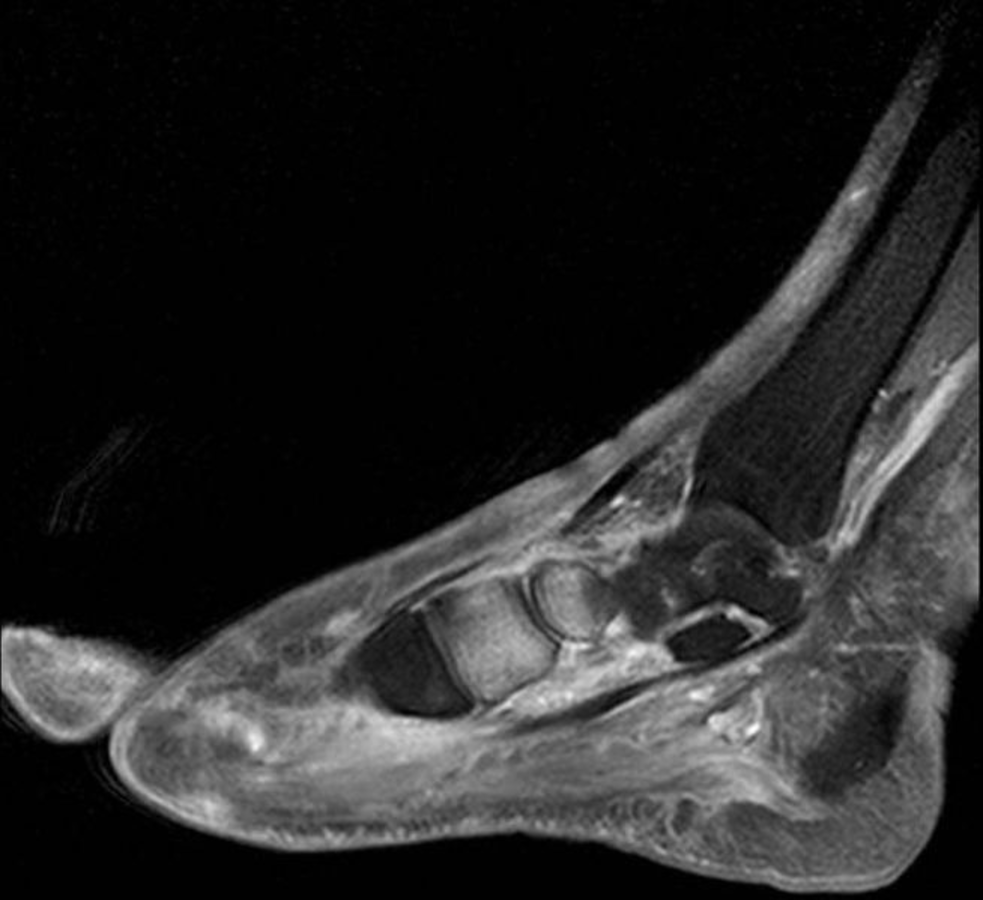

Geschwollener, schmerzunempfindlicher rechter Fuß ohne Hautverletzung bzw. Infektion bei Diabetes mellitus Geschwollener, schmerzunempfindlicher rechter Fuß ohne Hautverletzung bzw. Infektion bei Diabetes mellitus © wikimedia/Radschläger13 (CC BY-SA 4.0)